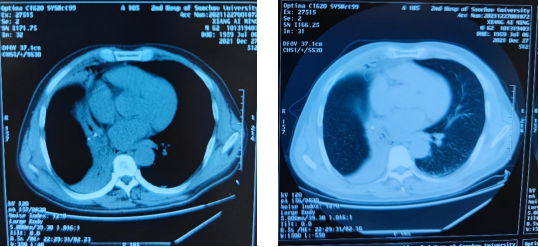

外院CT示阻塞性肺炎(纵膈窗) 外院CT示阻塞性肺炎(肺窗)

蒋主任接到电话后立即安排床位,做好各项准备工作。考虑患者为中年男性,现已出现高热反复,感染指标进行性升高,如异物无法取出,根本病因不能解决,感染会愈加严重,最终可能需手术切除右肺中叶、右肺下叶来避免感染性休克,甚至有致残、致命的风险。蒋军红主任团队与麻醉科李健主任医师团队探讨手术方式,因该异物异常坚硬,与支气管粘膜嵌合一起,随着病人每次呼吸,负压越大,嵌合越紧,常规气管镜及异物钳、冷冻等手段均难以取出,操作难度远比想象的困难得多,蒋军红主任运用高超的介入治疗技巧及耐心操作,最终花费了1个多小时,钳取出该艰难异物,赢得了手术室里所有人的欢呼与掌声。